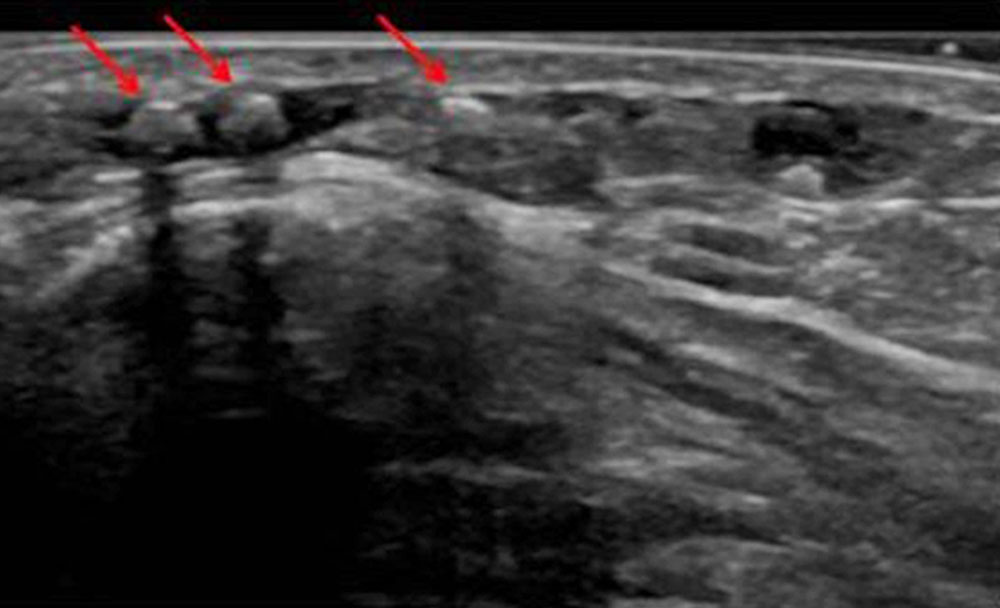

Video: Blood stasis within a venous malformation on ultrasound (B-scan). The very slow blood flow in the dilated vascular spaces of the VM results in the formation of small thrombi, which appear slightly more echogenic (light gray) in the sonogram in contrast to normally anechoic blood (completely black). © Wohlgemuth